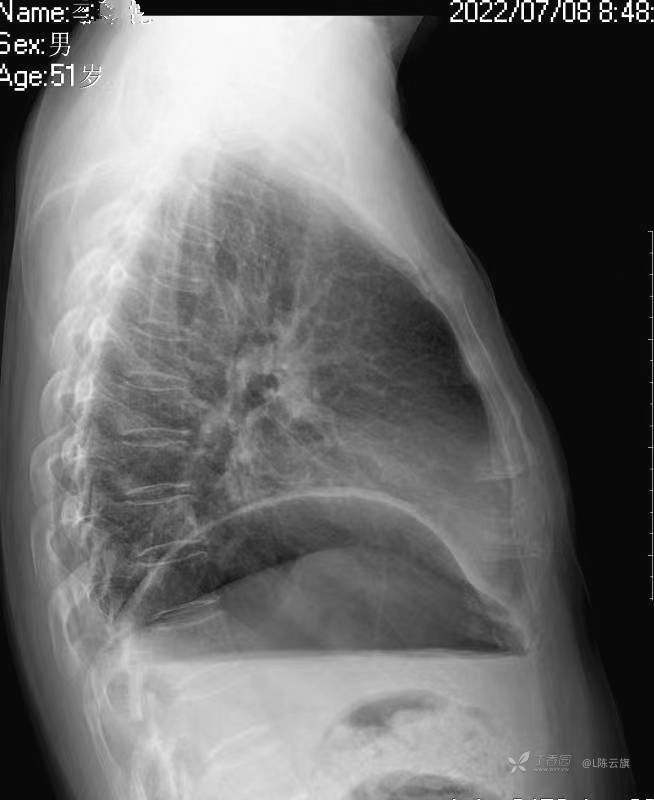

华夏览雄 达人已点赞1、患者男,51岁,精神病长期住院患者,主要病史只有时不时觉得腹部不适,其他不详。系列胸片为定期胸部检查。